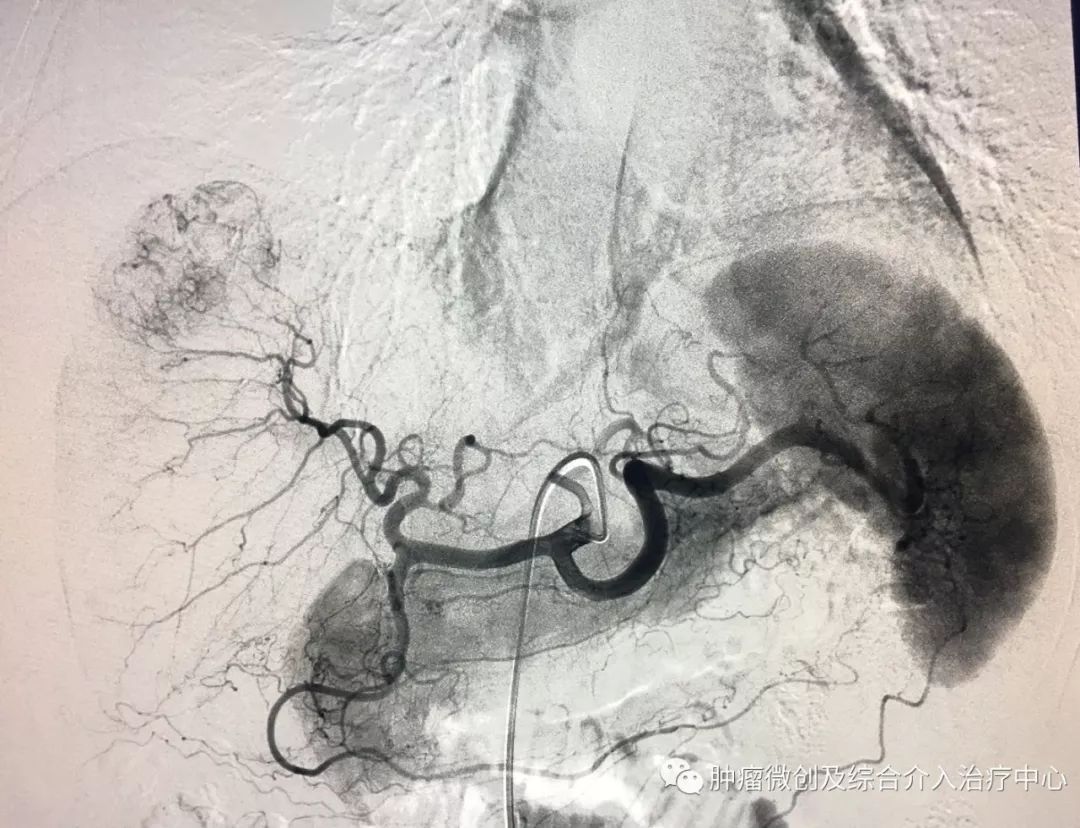

(鼻咽癌颈部转移瘤破溃出血,DSA造影提示左颈部病变血管迂曲、紊乱,内有出血)

(介入栓塞病变血管后,DSA示肿瘤病变血管栓塞好,血管走向清晰,出血停止)项目介绍:头颈部良、恶性肿瘤临床常见,其良性见于鼻咽纤维血管瘤,恶性者见于鼻咽、鼻窦癌,颈部转移性肿瘤等; 传统止血治疗疗效有限,给患者及家属带来极大的精神压力,介入手术栓塞病变血管可达到确切的止血效果,并致病变缺血萎缩。04急性肺栓塞介入手术治疗